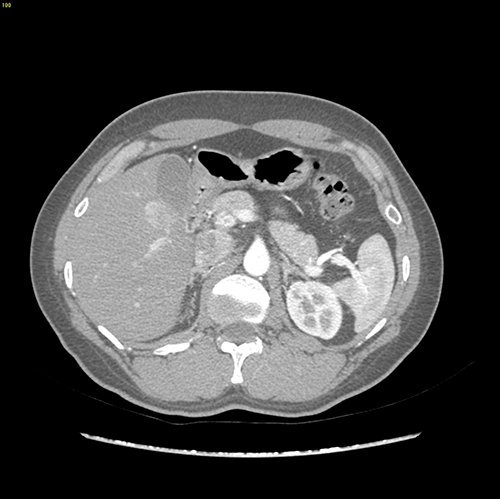

S5 肝癌--腹腔镜S5切除